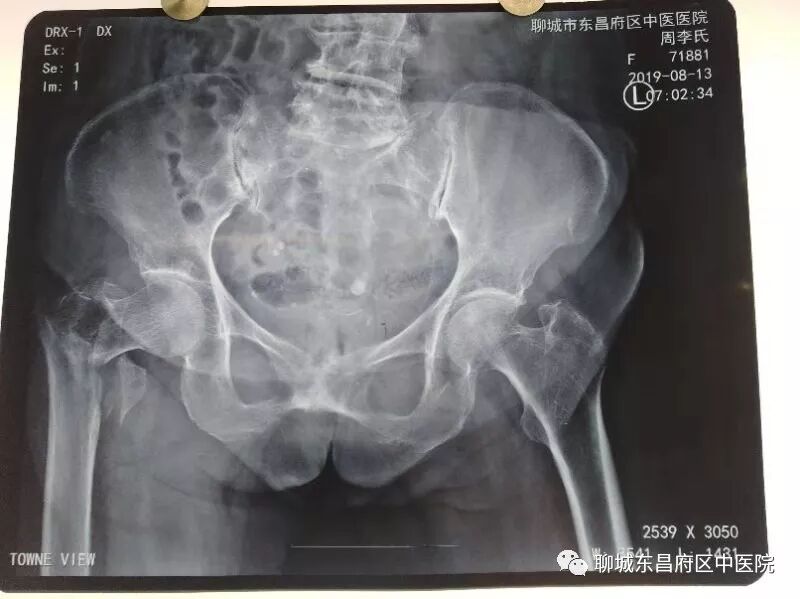

昨日,我院120接入一91岁高龄右股骨粗隆间骨折患者,入院后骨一科主任郭文青高度重视,对患者进行了初步查体,组织科室进行了风险评估,完善了入院相关检查,请麻醉科韩青主任进行了术前会诊。 经过详细的术前准备后,今日上午给予闭合复位PFNA内固定。患者90余岁高龄,各脏器已经严重衰老,对麻醉及手术的耐受能力已经很差,这已经给麻醉师提出了很严峻的考验,再加上患者驼背畸形,这就给麻醉穿刺带来了更大的困难。但我院手术室的同事们并没有被困难吓到,而是迎难而上,以精湛的技术,凭着过硬的基本功,顺利的完成了穿刺、置管、给药,整个过程患者病情非常稳定。该例股骨粗隆间骨折的手术,对于主刀医生也同样存在很大的困难。其一,该骨折为粉碎性骨折,虽为粗隆间骨折,但接近股骨颈,在复位时股骨头容易旋转,导致闭合复位失败。其二,患者骨质疏松严重,骨皮质很薄,在操作过程中很容易出现新的骨折,这就要求主刀医生在操作过程中要更加细心,准确。郭文青主任利用中医整复技巧,首先顺利的完成了整复,而后郭主任每一步操作都必须准确到位,经过40分钟紧张有序的忙碌,顺利的完成了手术,整个手术过程患者病情稳定,无疼痛及不适,术后往ICU继续治疗。